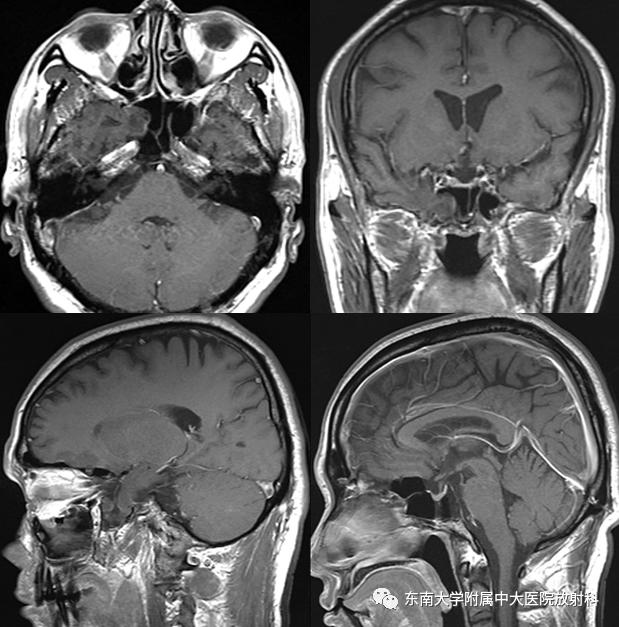

脑脊液鼻漏影像学评估

病史

• 男,53岁

• 反复右侧鼻腔流清水样鼻涕2年余,自觉流涕量增多4月余,咳嗽咳痰2周

• 感鼻塞,伴全身乏力,偶有头痛

CT平扫+MR增强